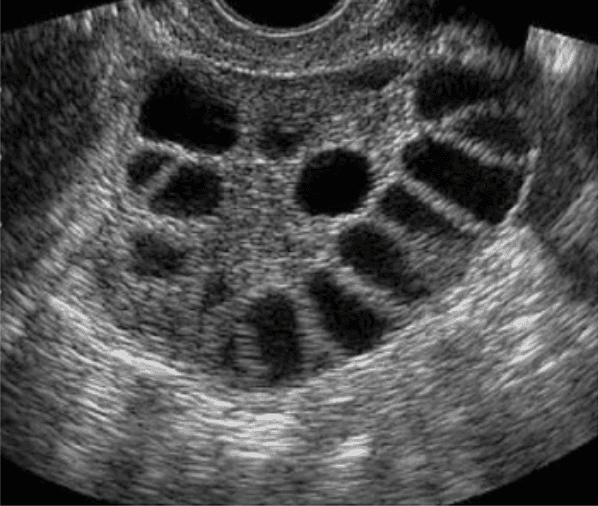

The name polycystic ovary syndrome describes the multiple small cysts which may be visible on your ovaries on ultrasound due to lack of ovulation (anovulation). However, despite the name "polycystic," you don’t need to have cysts on your ovaries to have PCOS. The ovarian cysts aren’t dangerous or painful.

• Cysts: Many people with PCOS have ovaries that appear larger or with many follicles (egg sac cysts) on ultrasound.

Ultrasound :

• This test is used to look at the size of the ovaries and see if they have cysts. The test can also look at the thickness of the lining of the uterus (endometrium).